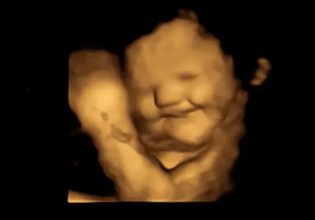

Μία νέα μελέτη από τη Δανία διαπιστώνει ότι η έκθεση μίας εγκυμονούσας σε τοξικά PFAS κατά το πρώιμο στάδιο της κύησης επηρεάζει την ποιότητα και ποσότητα του σπέρματος του εμβρύου.

Τα PFAS, ή αλλιώς πολυφθοριωμένες αλκυλιωμένες ουσίες, επηρεάζουν τις ορμόνες, την ανάπτυξη του εμβρύου αλλά και τη μελλοντική αναπαραγωγική του ικανότητα καθώς οι όρχεις αναπτύσσονται στη μήτρα κατά τη διάρκεια του πρώτου τριμήνου της εγκυμοσύνης, δήλωσε η συγγραφέας της μελέτης Sandra Sogaard Tottenborg του Πανεπιστημιακού Νοσοκομείου της Κοπεγχάγης.

Παρότι και στο παρελθόν είχαν γίνει ανάλογες έρευνες, αυτή είναι η πρώτη που εξέτασε την περίπτωση έκθεσης σε περισσότερα από δύο PFAS και τις επιπτώσεις της έκθεσης στην πρώιμη εγκυμοσύνη, όταν και αναπτύσσονται τα ανδρικά αναπαραγωγικά όργανα.